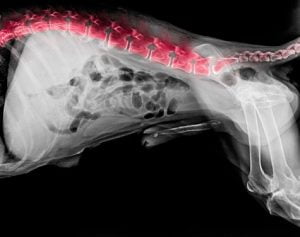

Pour poser le diagnostic d’un syndrome de la queue de cheval, le vétérinaire doit avoir recours à une électromyographie et/ou à des examens d’imagerie tels que la radiographie, le scanner ou l’IRM.